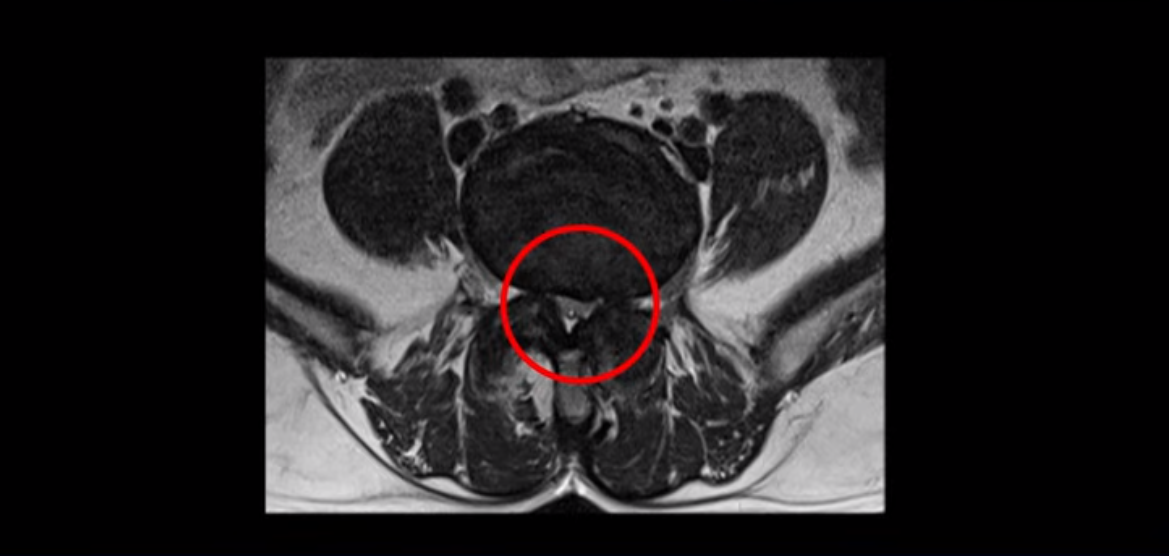

하지만 중심성 협착은 여전히 심한 상태입니다.

이분은 오른쪽, 왼쪽 다리에 모두 방사통이 심하고 왼쪽 다리에 마비 증상, 즉 풋드랍(족하수) 증상이 있습니다. 왼쪽 신경 가지가 빠져나가는 추간공을 보면 두 마디가 좁아져 있습니다.

이런 신경 구멍이 좁아져 있는 걸 협착이라고 합니다.